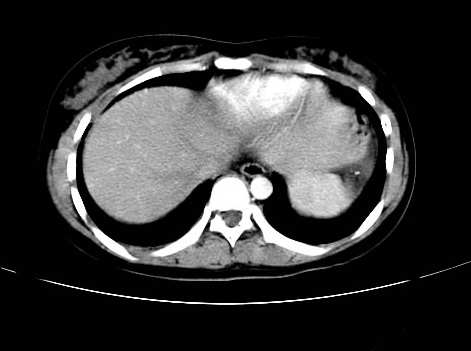

女 16岁  右上腹痛一天,无其他不适

肿块最大径位于十二指肠降段与水平段移行处,并且与肝脏压迹呈“0”形征,可以考虑位于肝外并与胃肠道关系紧密,考虑胃肠道间质瘤(gist)可能较大,须除外神经节起源肿瘤。

肿块与十二指肠关系密切,支持间质瘤诊断.肝脏与结肠均为受压改变.

右下腹巨大肿快,密度不均匀,内见坏死低密度区,边界清楚,与周边胀器明显有分界,未见强化,多考虑来源于间叶组织的良性肿物.

我坚决反对您的观点,该病例定位:横结肠肝曲与升结肠之间的肠系膜及部分肠壁。请看下图:

病灶巨大,少部分向肠腔内生长,大部分向长腔外生长。其密度不均匀,增强显示明显不均匀强化,并见有大片状始终不强化的不规则坏死液化区。虽然病灶中上部形态尚可,病人又如此年轻,但中下部形态、密度、强化特点强烈提示为恶性病灶。综上,我考虑本病例为:恶性胃肠道间质瘤。